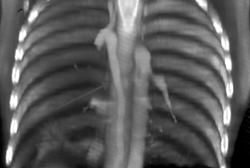

Bronchogenic Cyst